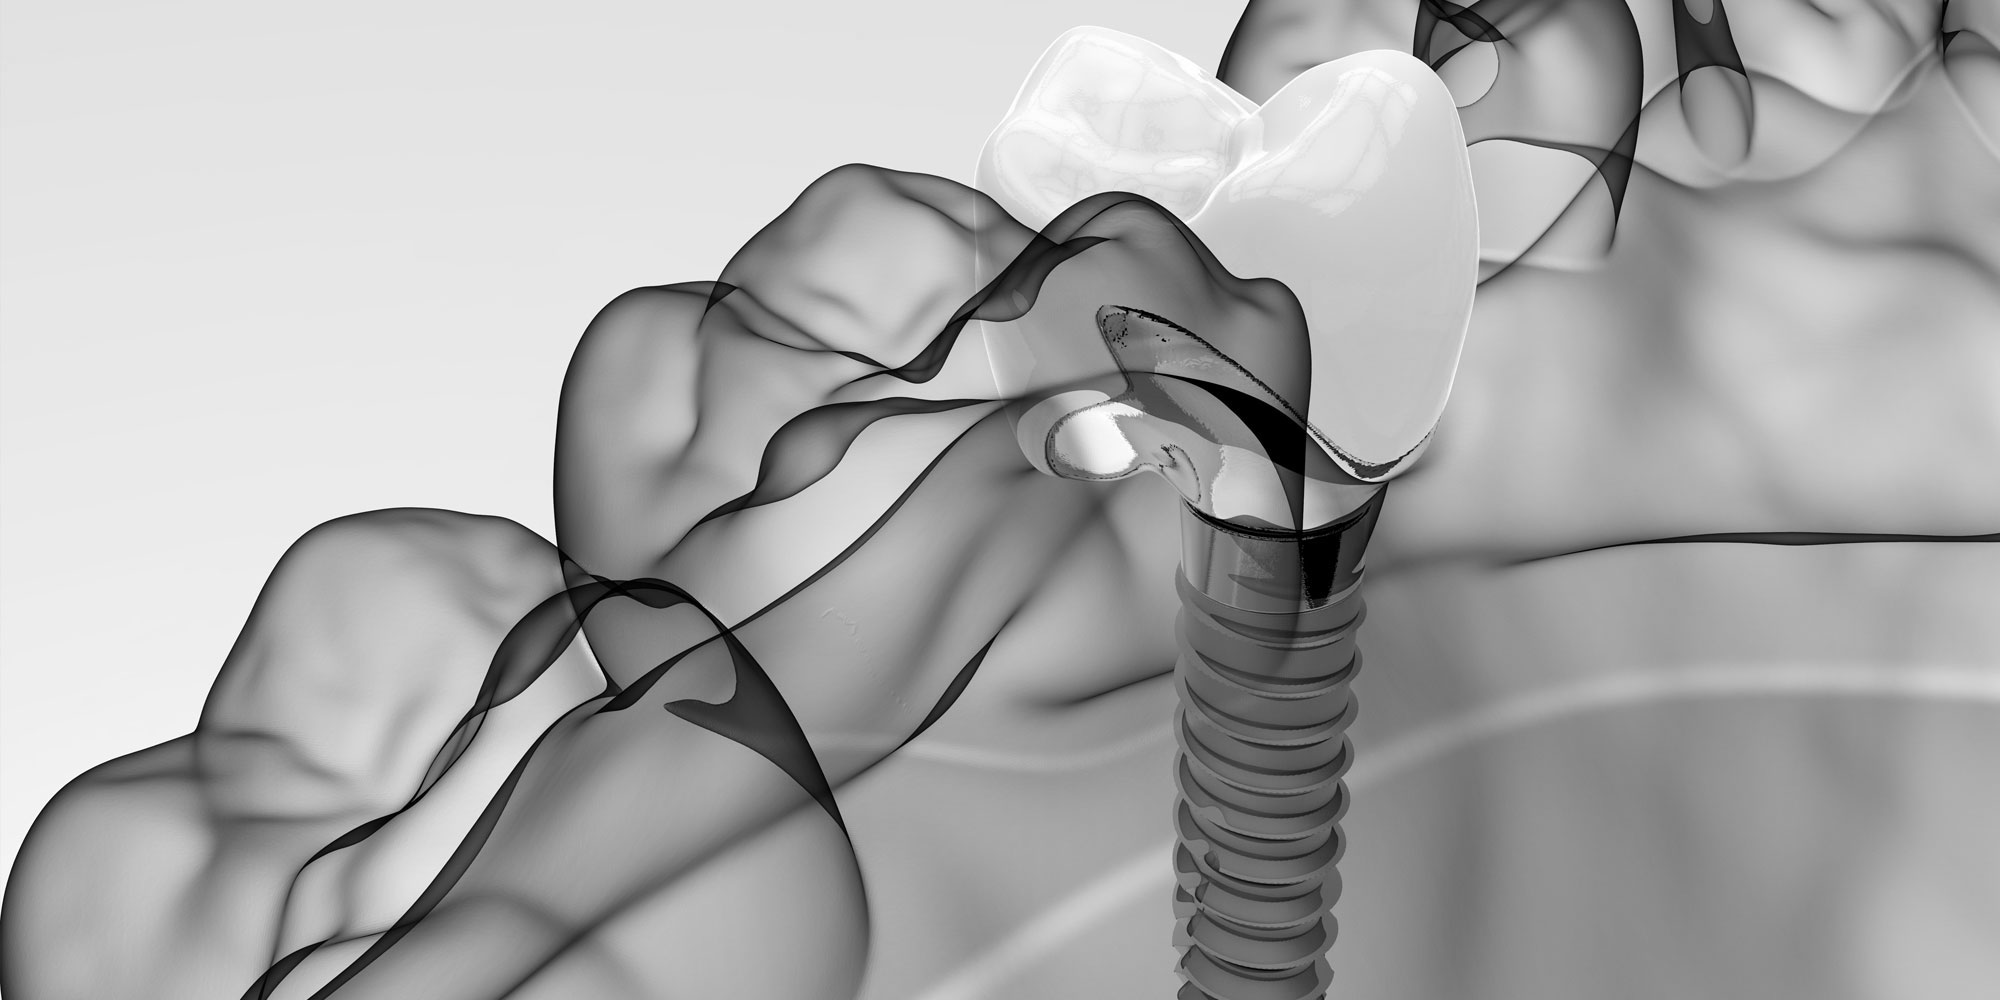

It’s not anything near the long, uncomfortable procedure many people may imagine they’ll need to undergo in order to get dental implants. Thanks to innovations

Dental implants are becoming an increasingly popular option for people who have one or more missing teeth. However, some patients are still a bit apprehensive

There are many health benefits to dental implants such as how they keep jaw bone density resilient and prevent surrounding teeth from shifting. However, many patients

Many patients are unaware of what makes a periodontist different than a general dentist, especially when it comes to the placement of dental implants. A

You want to restore your smile but you know it could take weeks or even months to complete the process with traditional dental implants. This

Did you know that approximately 120 million Americans are currently missing at least one tooth, according to data released by the American College of Prosthodontists?